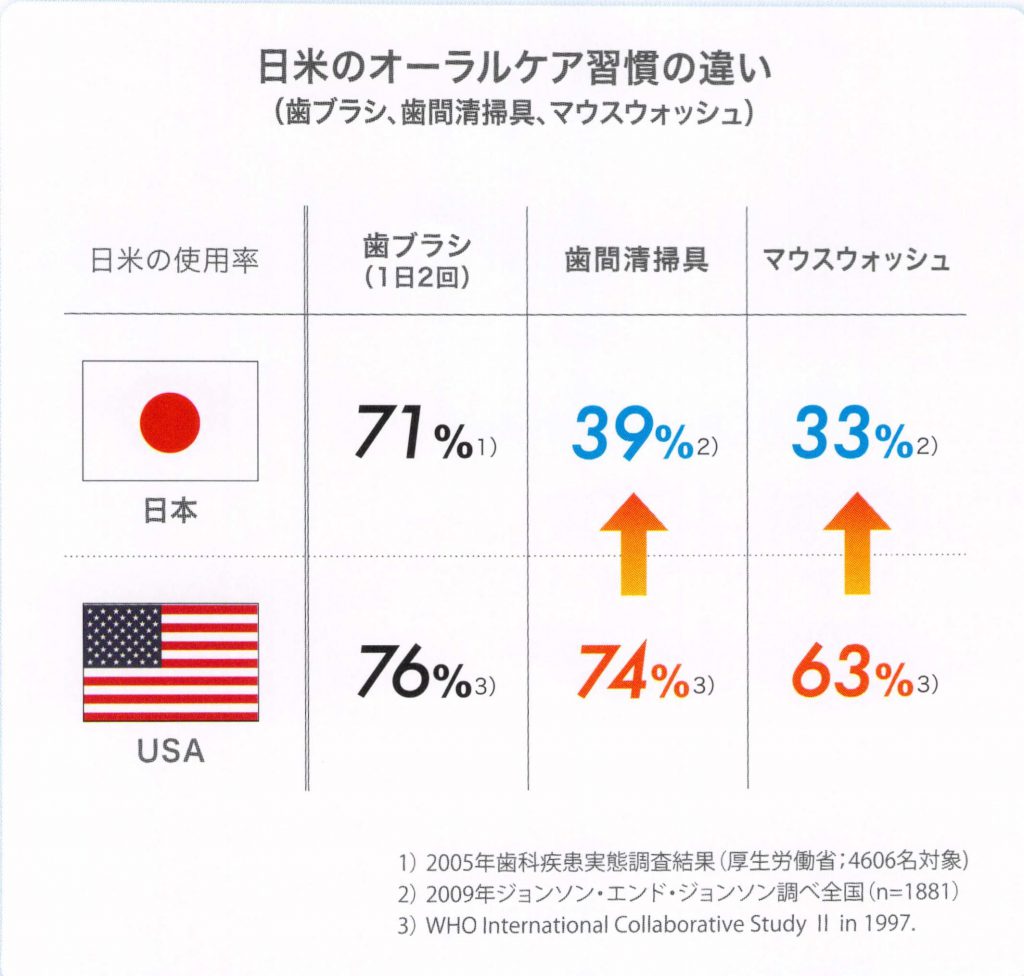

日本人の

成人の80%が歯周病菌に感染し、

歯周病だと言われています